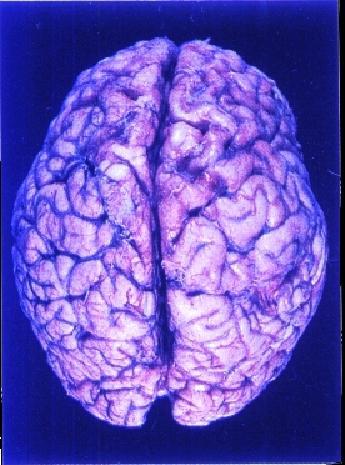

Nein, genau symmetrisch sind die, den Beobachtenden häufig rosa-grau erscheinenden, Hälften des Cerebrum (Grosshirns) nicht! Durch einen (Quer-)'Balken' (Corpus Callosum), aus 'weissen' Nervenfasern, verbunden, sind beide 'Hemisphären' weitgehend vom sehr falten- und windungsreichen Neokortex (der 'Großhirnrinde') umgeben, - dessen 'Feldern' allzu gerne ordnend und mit (letztlich neuro-)wissenschaftlicher Akribie, die hauptsächliche 'Zuständigkeit' für bestimmte Aufgabenbereiche 'zulokalisiert' werden. |

Draufsicht – Nase oben |

Diese, mit Abstand, grössten, zum Gehirn des Menschen gerechneten, Teile (85%) bedecken bzw. umschliessen wichtige andere (Gehirn-)Regionen, mit denen sie vielfachst verbunden - hervorragend geschützt und gedämpft, in Flüssigkeit schwebend, im Schädel gelegen – zusammenarbeiten. |

Großhirn (Cerebrum) 4/5 d.h. 85%

Schließlich stellt das Großhirn bzw. die Großhirnrinde den phylogenetisch jüngsten aber

auch den größten Teil dar und ist für die höheren psychischen Prozesse wie Wahrnehmung, Gedächtnis, Lernen, Denken und Sprache etc. unentbehrlich. Von seiner Lage her

wölbt es sich über die anderen Gehirnabschnitte.. .... Sogenannte Sulci

(Furchen) trennen die Hirnwindungen voneinander. So wird das Großhirn durch eine

tiefe Längsfurche (Fissura longitudinalis) in zwei

Hemisphären (linke - rechte) unterteilt, die alleine durch den Balken (CC) miteinander

verbunden sind. Dieser macht eine effiziente Zusammenarbeit beider Hemisphären möglich.